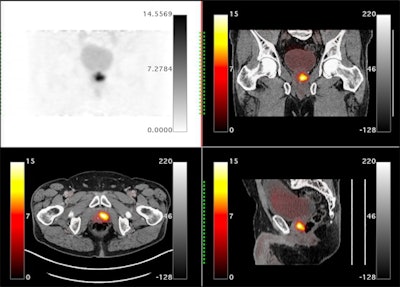

In this study, the authors aimed to measure the accuracy of two PSMA-PET tracers for assessing this so-called "extraprostatic extension" (EPE) at nerve bundles.

The researchers retrospectively studied the imaging of 71 patients who underwent PSMA-PET scans prior to robotic prostatectomy. Two PSMA-PET tracers were used: gallium-68 (Ga-68) PSMA-11 (n = 46) and Ga-68 P16-093 (n = 25). The Ga-68 P16-093 tracer has up to three times less excretion in urine compared to Ga-68 PSMA-11, which is a potential advantage for pelvic imaging, the authors noted.

According to the findings, 24 patients (34%) had EPE at nerve bundles near the prostate and 16 (23%) had prostate cancer invasion of seminal vesicles. The sensitivity, specificity, and area under the receiver operating characteristic curve (AUC) for identifying EPE were similar between the two tracers, according to the findings.